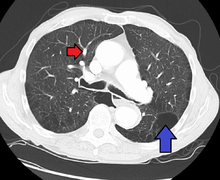

In terms of the diagnosis of pulmonary hypertension, dictates it can be of five major types, a series of tests must be performed to distinguish pulmonary arterial hypertension from venous, hypoxic, thromboembolic, or miscellaneous varieties. Further procedures are required to confirm the presence of pulmonary hypertension and exclude other possible diagnoses. These generally include pulmonary function tests; blood tests to exclude HIV, autoimmune diseases, and liver disease; electrocardiography (ECG); arterial blood gas measurements; X-rays of the chest (followed by high-resolution CT scanning if interstitial lung disease is suspected); and ventilation-perfusion or V/Q scanning to exclude chronic thromboembolic pulmonary hypertension.[27][28] Clinical improvement is often measured by a "six-minute walk test", i.e. the distance a patient can walk in six minutes. Stability and improvement in this measurement correlate with better survival.[29]